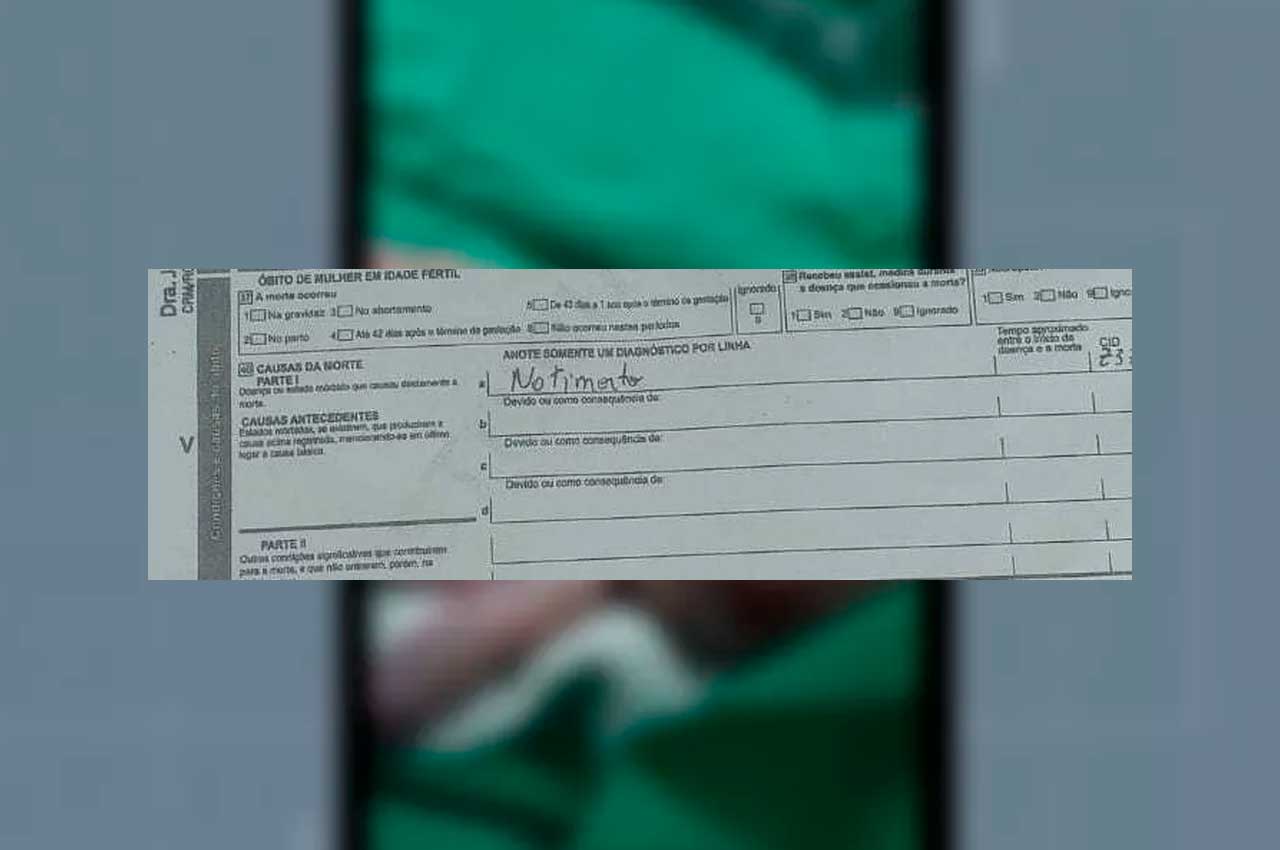

PC investiga morte de bebê encontrado com queimaduras nas mãos em Maceió

Os pais do bebê foram encaminhados pelos policiais até a Central de Flagrantes para mais esclarecimentos sobre a morte dele.